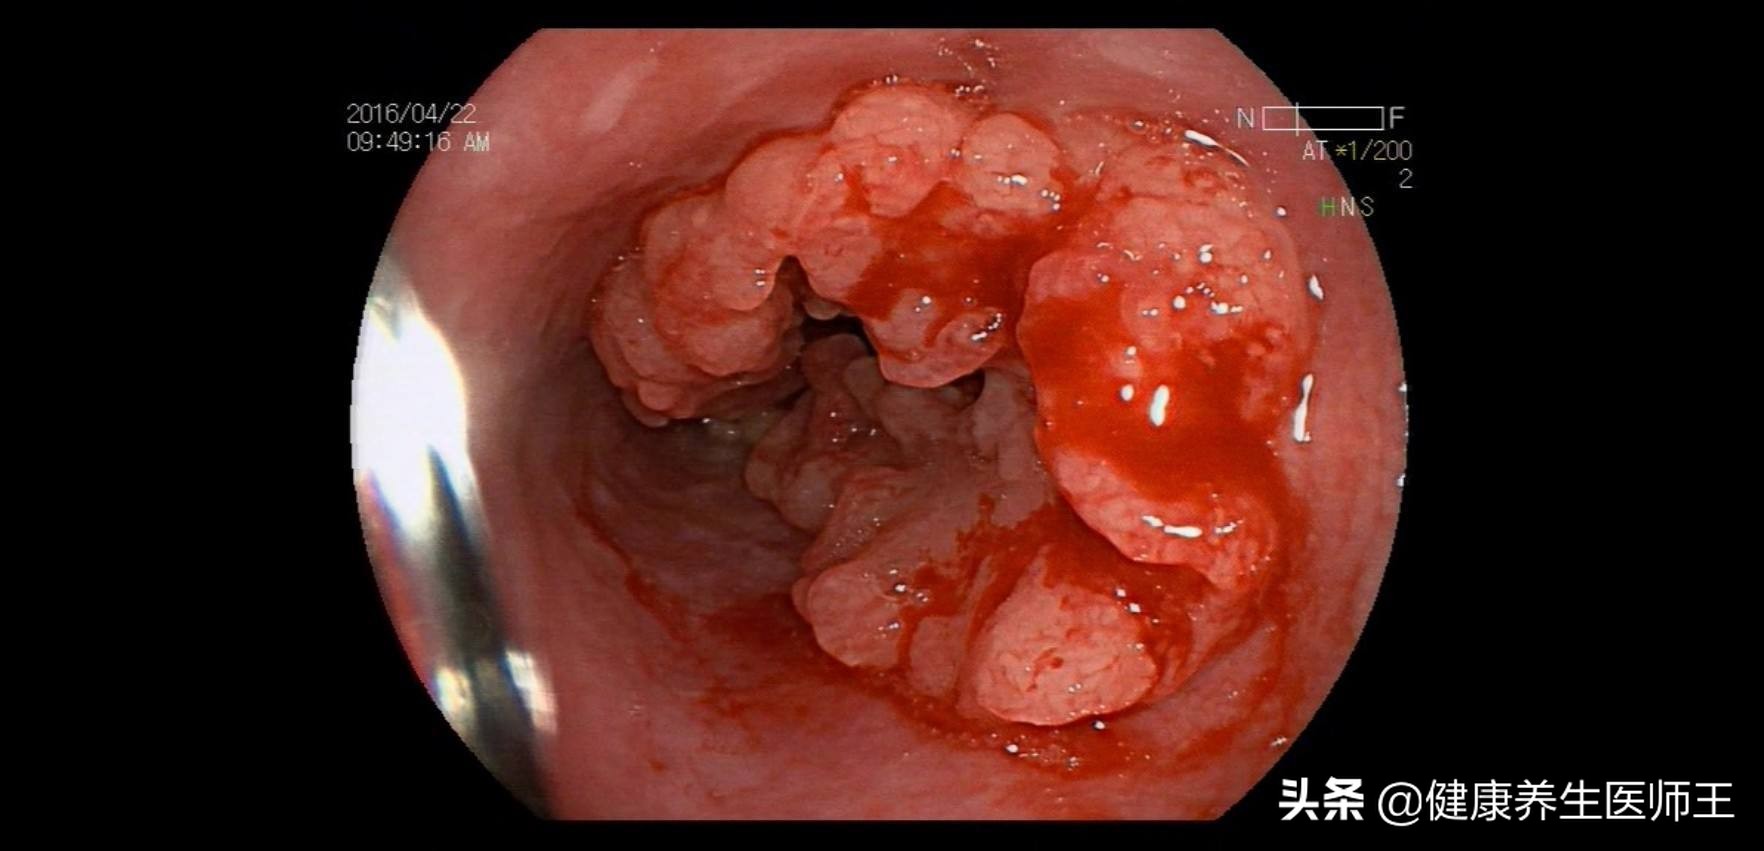

1.胃镜 是食管癌诊断的首选方法,可直接观察病灶形态,并取活检以确诊。色素内镜、电子染色内镜、放大内镜及共聚焦激光显微内镜等可提高早期食管癌的检出率。

1.早期食管癌 病灶局限于黏膜层和黏膜下浅层,不伴淋巴结转移。胃镜下呈充血、斑块、糜烂充血型多为原位癌,是食管癌的早期表现;斑块型最多见,癌细较差;乳头型主要为早期浸润癌癌细胞分化一般较好。

2、中晚期食管癌癌组织逐渐累及食管全周突入腔内或穿透管壁侵质型、蕈伞型、溃疡型和缩窄型。